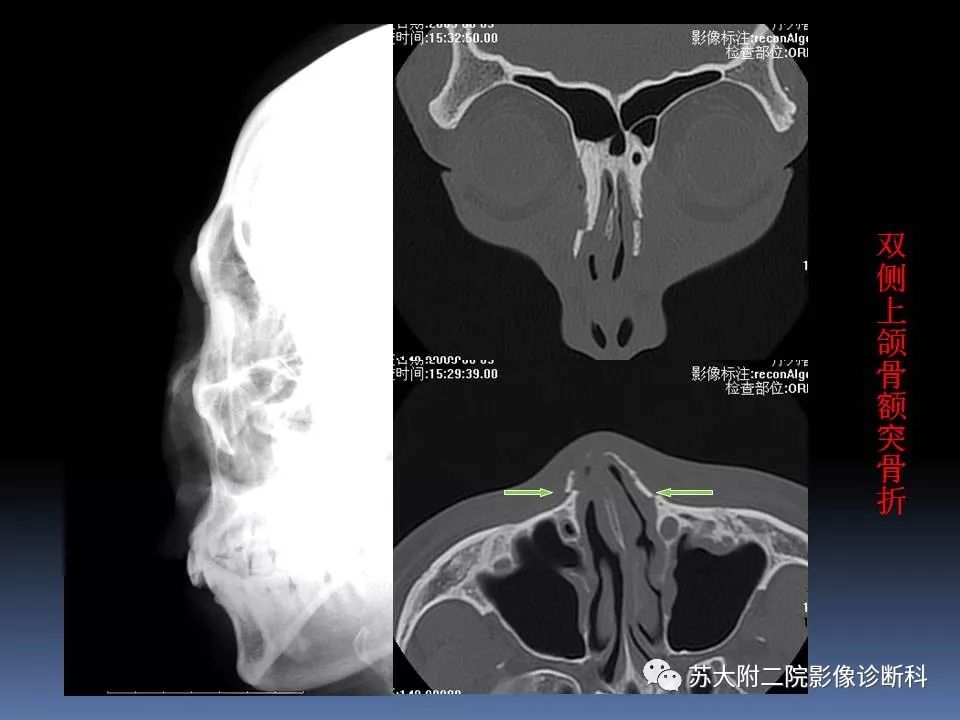

【PPT】鼻骨骨折影像诊断误区-1